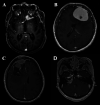

Meningiomas are the most the common primary brain tumors in adults, representing approximately a third of all intracranial neoplasms. They classically are found to be more common in females, with the exception of higher grades that have a predilection for males, and patients of older age. Meningiomas can also be seen as a spectrum of inherited syndromes such as neurofibromatosis 2 as well as ionizing radiation. In general, the 5-year survival for a WHO grade I meningioma exceeds 80%; however, survival is greatly reduced in anaplastic meningiomas. The standard of care for meningiomas in a surgically-accessible location is gross total resection. Radiation therapy is generally saved for atypical, anaplastic, recurrent, and surgically inaccessible benign meningiomas with a total dose of ~60 Gy. However, the method of radiation, regimen and timing is still evolving and is an area of active research with ongoing clinical trials. While there are currently no good adjuvant chemotherapeutic agents available, recent advances in the genomic and epigenomic landscape of meningiomas are being explored for potential targeted therapy.